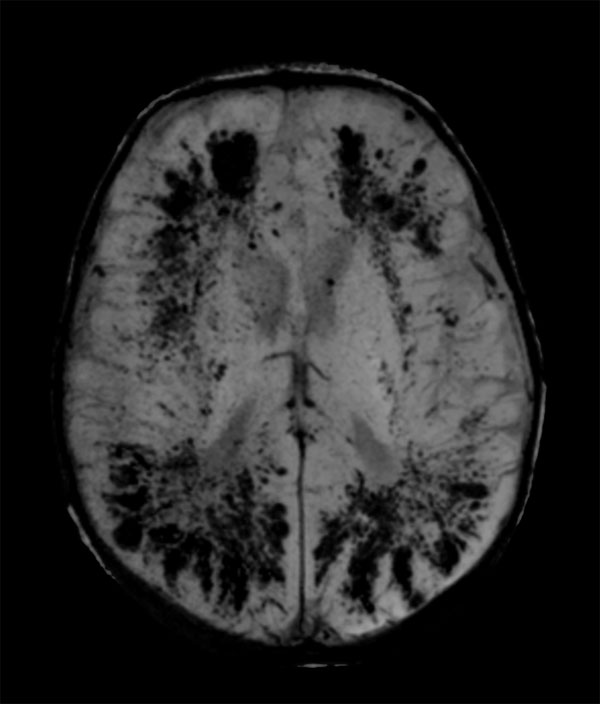

SWIp

Axial SWIp